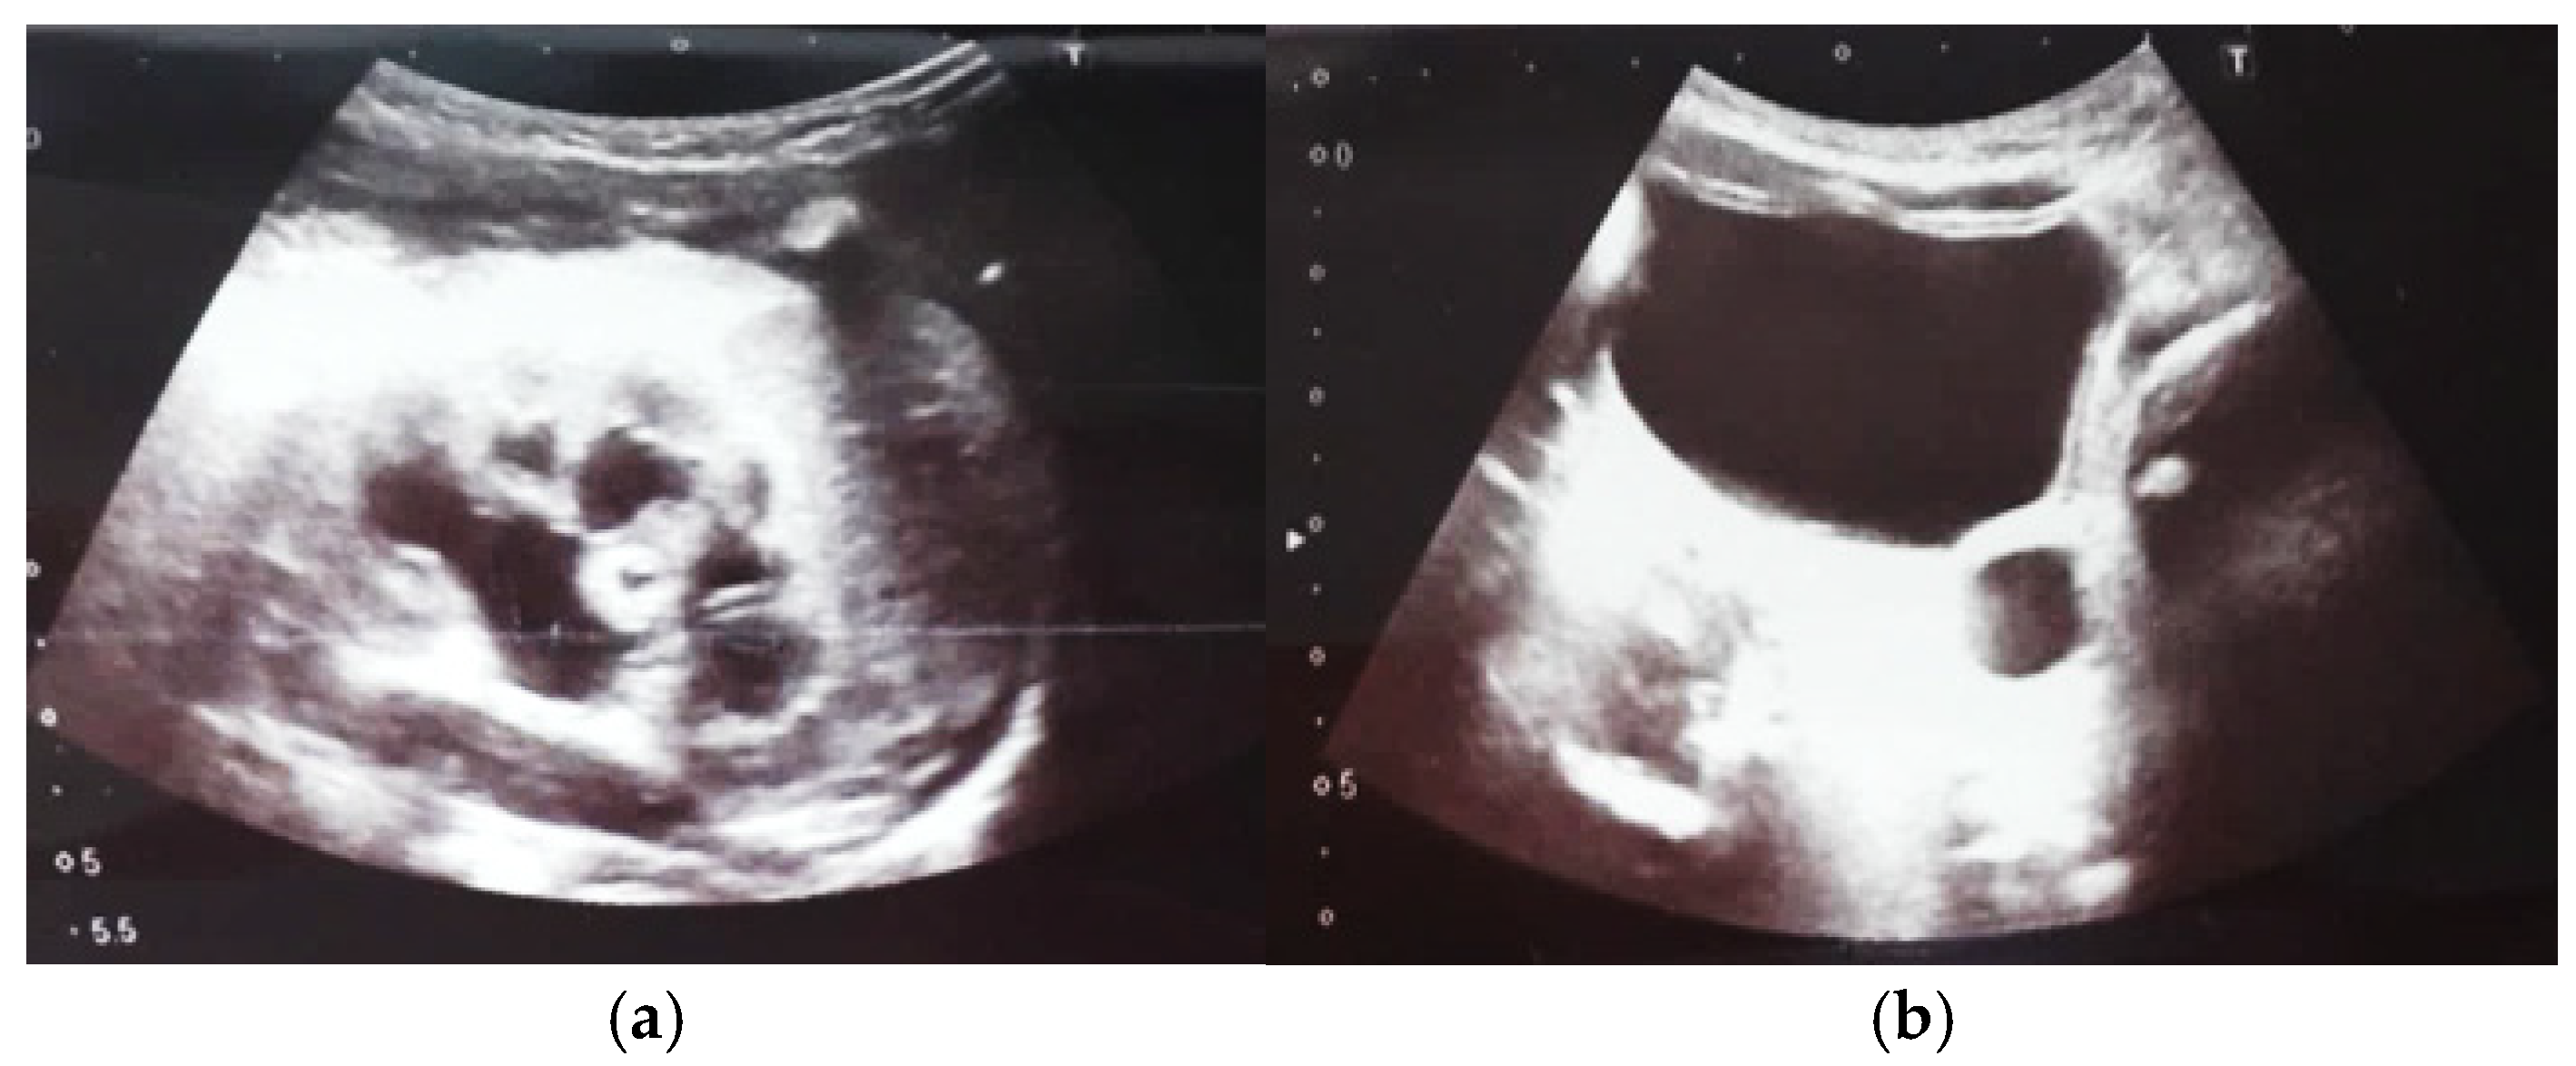

Our experience with congenital malformations of the urinary system refers to the following clinical case (Figure 2, Figure 3, Figure 4, Figure 5, Figure 6, Figure 7, Figure 8 and Figure 9). In the first case, during pregnancy, the 21-week ultrasound determined bilateral renal pyelectasia. The fetus had hydronephrosis on the right; at 31 weeks, it had bilateral hydrocalconephrosis; and at 32 weeks, bilateral pyelectasia. It suffered premature birth at 36 weeks, with complicated anomalies of the forces of contraction, prolonged birth, and birth weight of 2200 g. Postnatal ultrasonography was supplemented by intravenous urography, and bilateral hydronephrosis was determined. Hydrocalconephrosis on the left was discovered. The complete diagnosis was established: congenital renal malformation; bilateral pyelectasia; bilateral hydronephrosis; hydrocalconephrosis on the left; and severe reduced glomerular filtration rate (GFR), GFR > 2SD below mean.

Figure 9. Ultrasound of the urinary system in a 12-day-old newborn. Hydrocalconephrosis on the left (a) and ureteral hydronephrosis on the right (b).